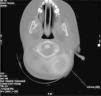

La radiografía de rodillas mostró desflecamiento de ambos cóndilos femorales mediales y en la radiografía de comparada de tobillos se encontró un punto de osificación en el izquierdo (fig. 1) que no estaba en el pie derecho, pudiendo corresponder a un proceso inflamatorio antiguo. En la ecografía de rodillas, se observó de forma bilateral imagen indicativa de colección líquida con densidad interna heterogénea, mal definida, a nivel de la bursa suprarrotuliana. Hallazgo sugestivo de bursitis. Midió de forma aproximada unos 13×5mm en el lado derecho y 23×5mm en el izquierdo (fig. 2).

Ecografía de rodillas. Se observa de forma bilateral imagen indicativa de colección líquida con densidad interna heterogénea, mal definida, a nivel de la bursa suprarrotuliana. Hallazgo indicativo de bursitis. Mide de forma aproximada unos 13×5mm en el lado derecho y 23×5mm en el izquierdo.